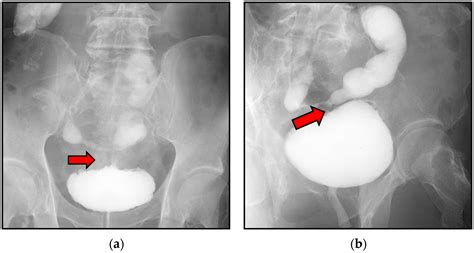

Voiding Cystourethrogram (VCUG) An X-ray procedure that shows the bladder filling and emptying; excellent for identifying diverticula.